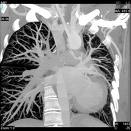

The study by Jörg Hausleiter, M.D., in the February 4 issue of the Journal of the American Medical Association correctly focuses on what providers need to know to ensure that computed tomography angiography (CCTA) is utilized appropriately.

Even with the collective efforts to reduce radiation exposure, it’s important to point out that CCTA, when used appropriately, minimizes other risks that more invasive procedures present to patients. Moreover, peer-reviewed research proves that CCTA is more cost effective than catheterization for some cardiac patients.